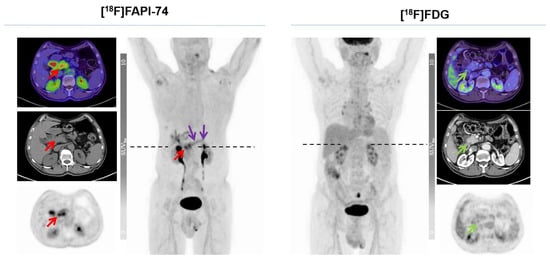

3.4. [18F]FAPI-74 in PDAC with Confounding Pancreatitis